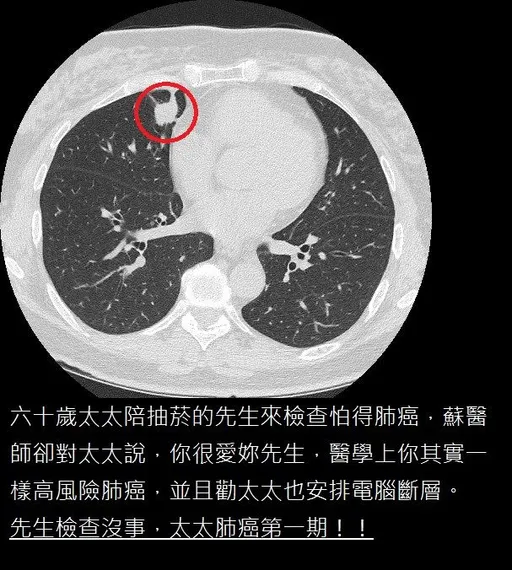

...危險群,在說服兩人都同時安排低劑量電腦斷層後,發現老菸槍的先生沒事,不抽菸的太太反而被發現已是肺腺癌...